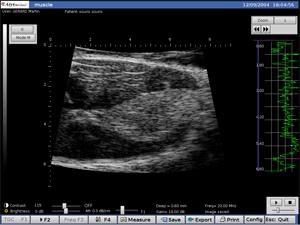

Ratón Músculo

El DERMCUP es un corte vertical in vivo no invasivo: 16 mm x 12 mm.

Gracias a su frecuencia de 25 MHz, el SHERPA ofrece alta resolución:

Axial: 30 m

lateral: 120 m

Adquisición de imágenes en tiempo real

La frecuencia de adquisición es de 10 cuadros por segundo.